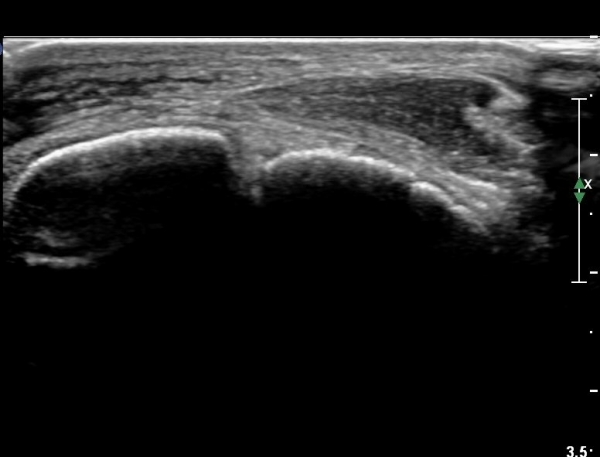

Àü°ÅºñÀδë Á¾´Ü¸é°Ë»ç¿¡¼­ Àü°ÅºñÀδëÀÇ ÆÄ¿­ÀÌ °üÂûµÈ´Ù(»çÁø 4, 5).

Àü°ÅºñÀδë Àü¹æ°ßÀΰ˻翡¼­ ÀÎ´ë ÆÄ¿­¿¡ ÀÇÇÑ °Å°ñÀÇ °úµµÇÑ ¿òÁ÷ÀÓÀÌ °üÂûµÈ´Ù(µ¿¿µ»ó Âü°í)